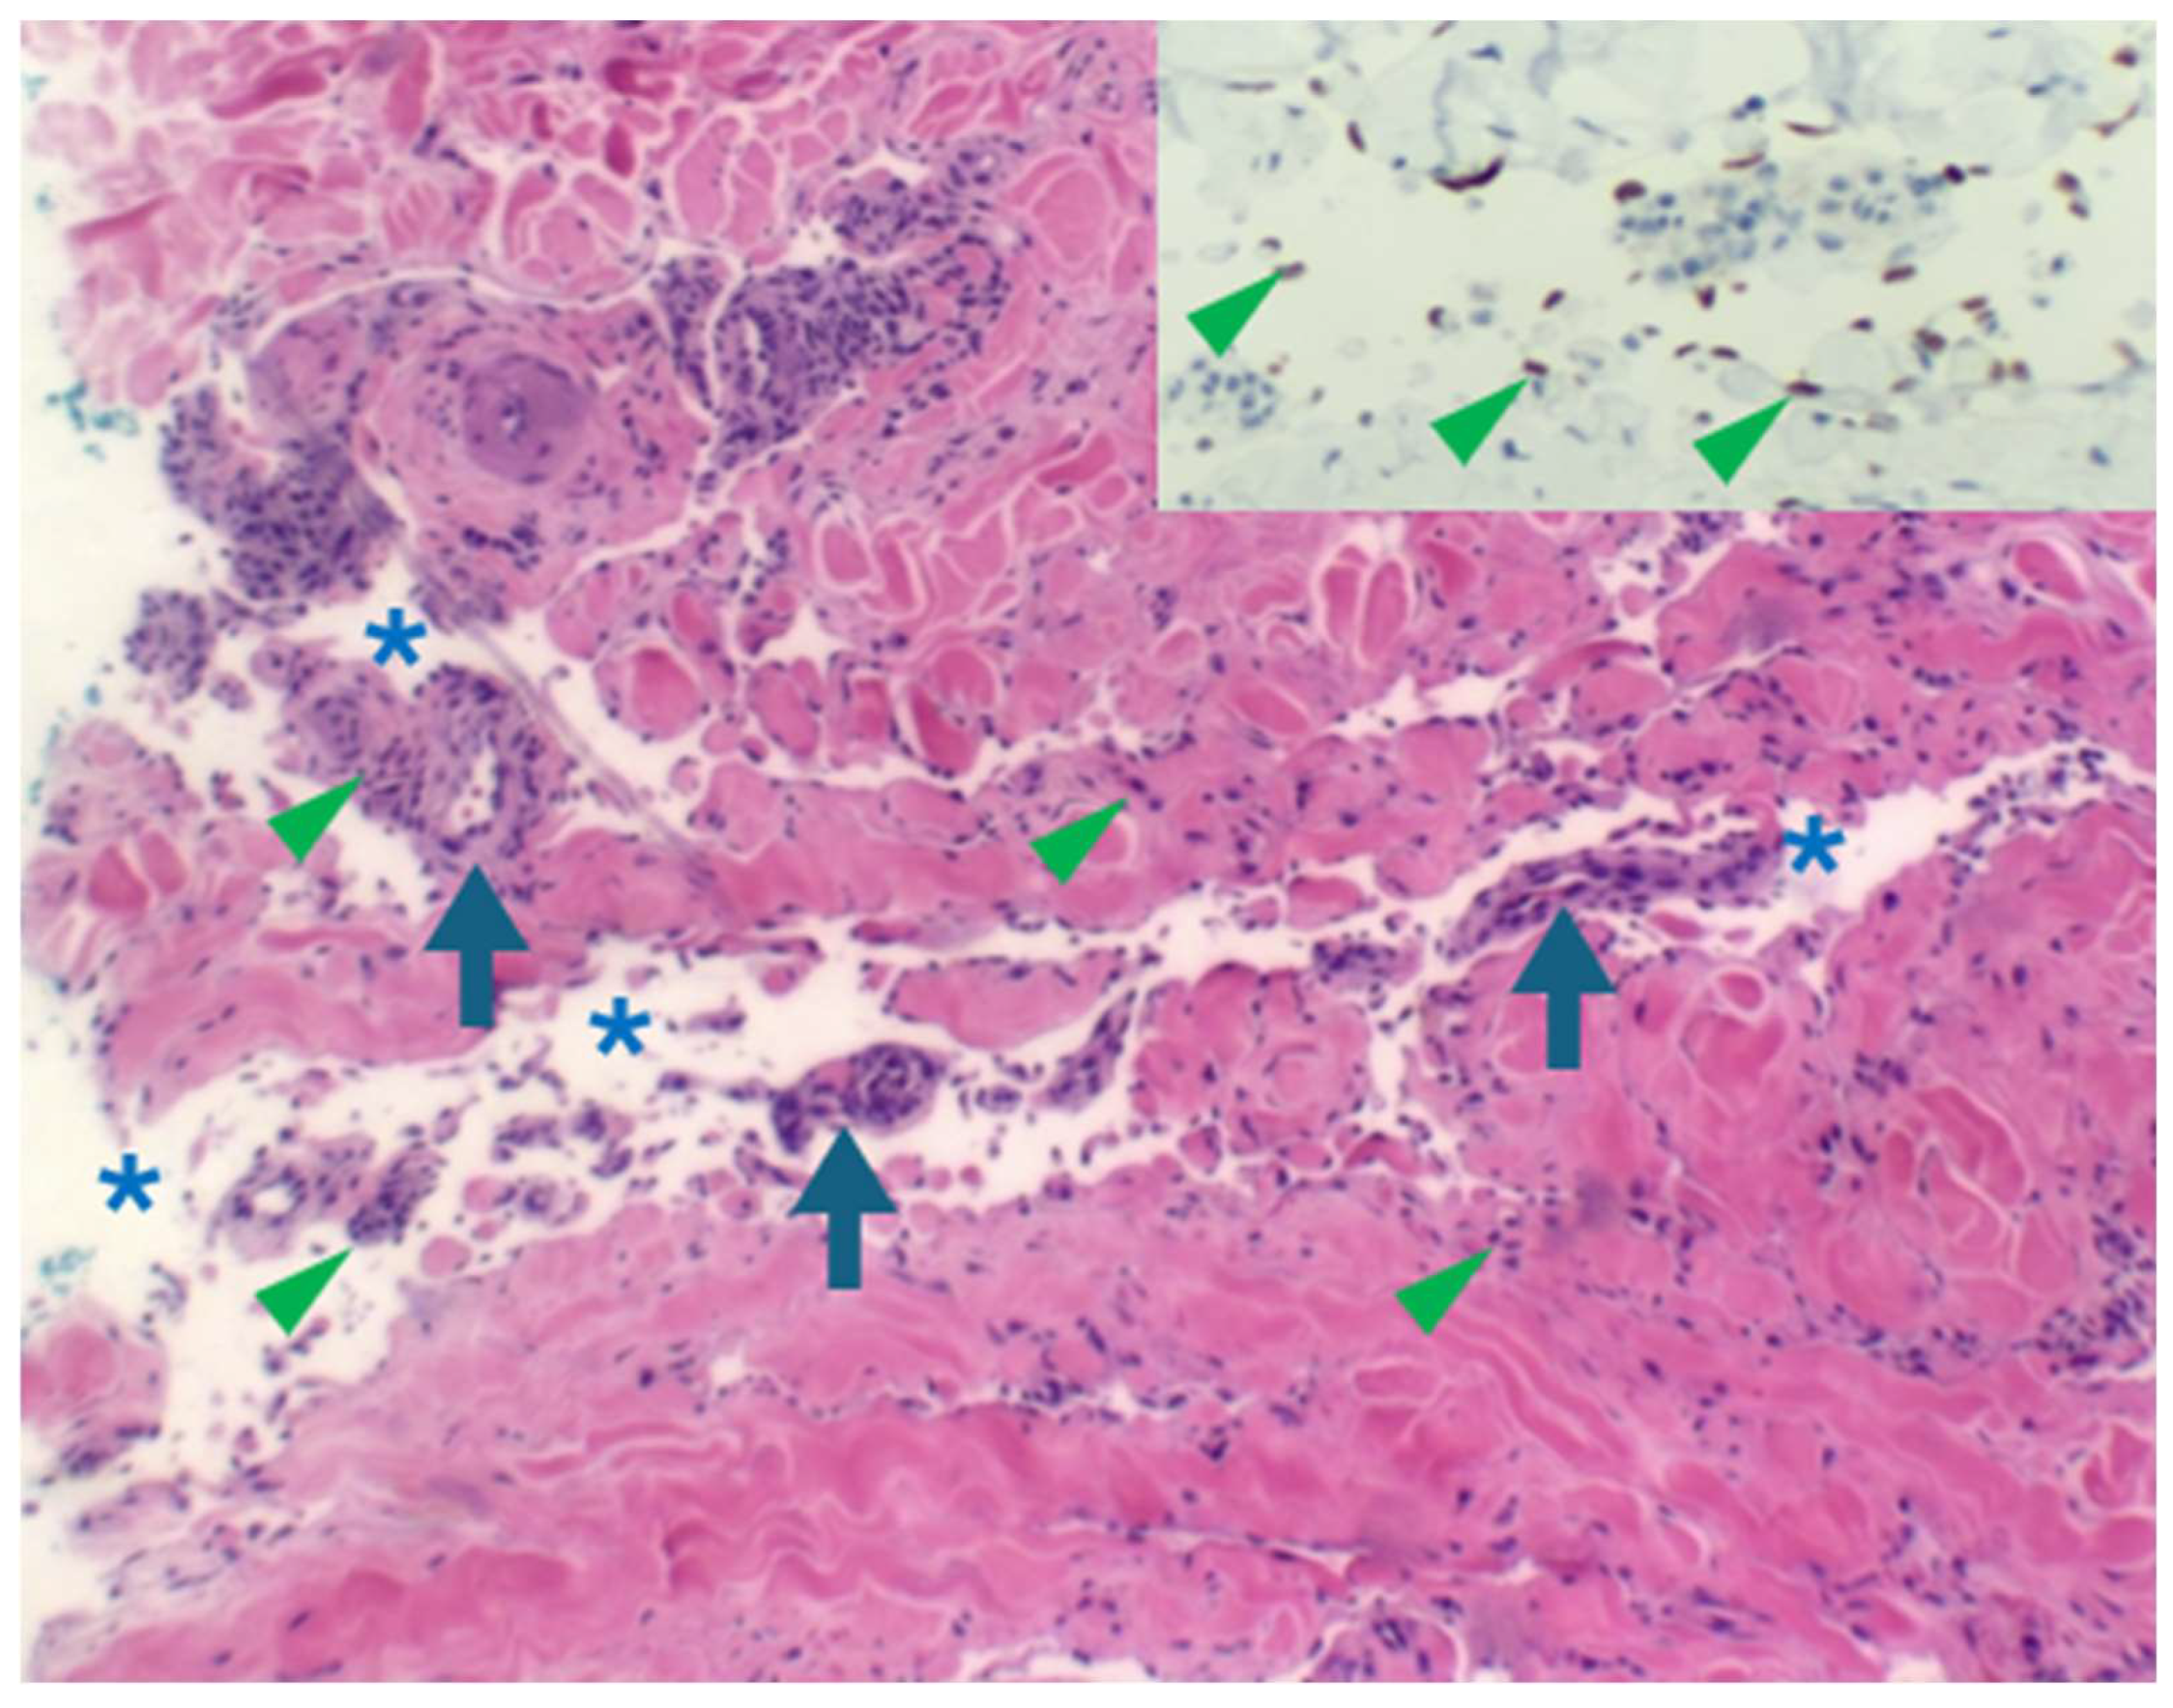

Figure 4.

Early lesion with a patch stage morphology demonstrating the “promontory sign” (haematoxylin and eosin in which a space (asterisks) surrounds vessels (arrows) and scattered spindle cells (arrowheads). HHV8 staining of endothelial cells (inset) confirms the diagnosis of early KS.